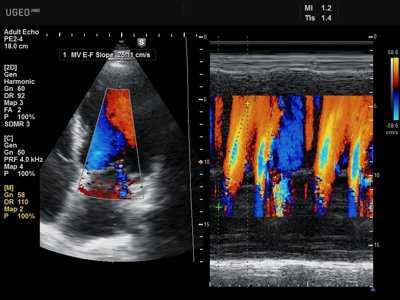

- Основные допплерографические характеристики трансмитрального и транстрикуспидального диастолического потока

- Е - раннее диастолическое наполнение (Vmax = 70-100 см\с)

- А - позднее диастолическое наполнение (в момент систолы предсердий, Vmax = 40-70 см\сек)

- Е\А = 1,0-1,5